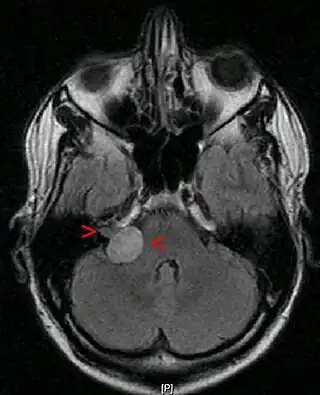

Neurinoma acústico con un tamaño de 20 x 22 x 25 mm. RMN en corte axial a nivel de los globos oculares.

Resonancia magnética con contraste.